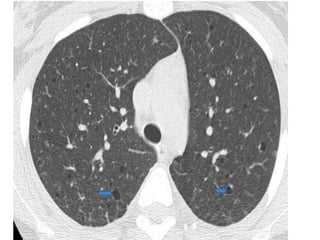

• #38 Chest CT scan: Multifocal pulmonary cysts characteristic of lymphangio-myomatosis (LAM)